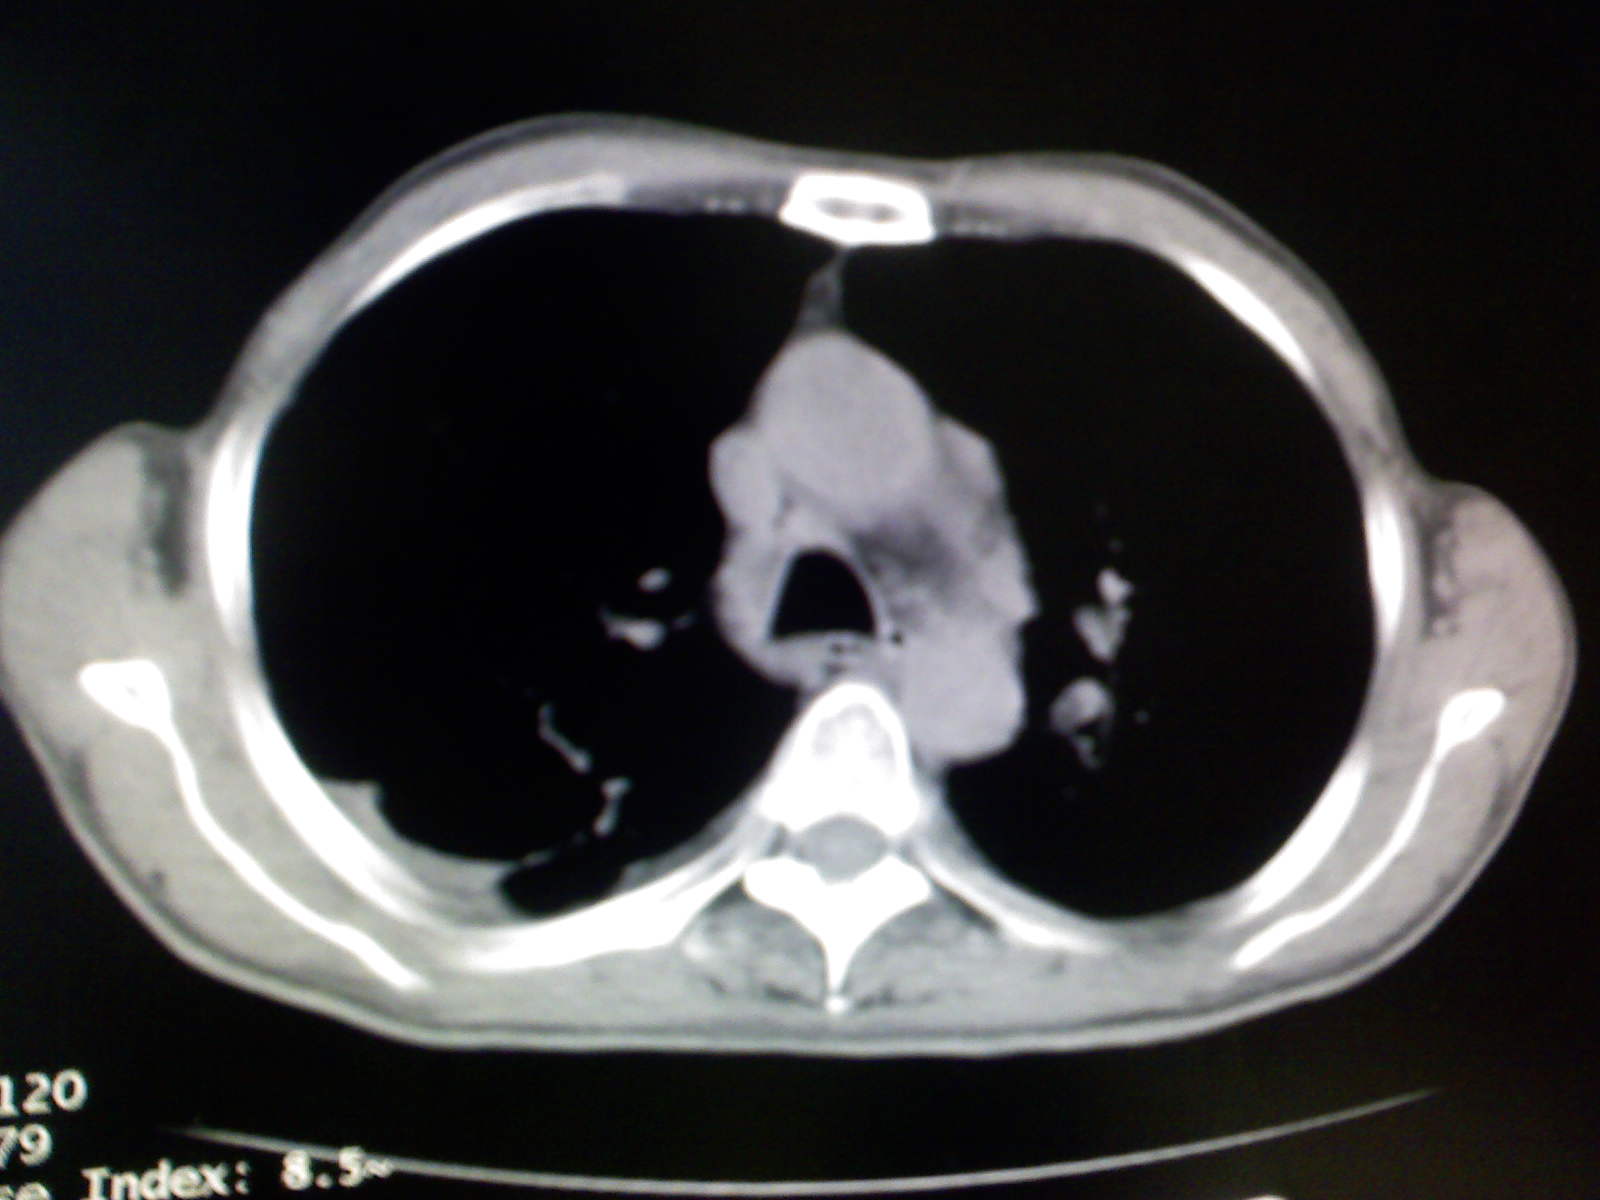

以下是引用卜一在2009-4-11 15:50:00的发言:[br]双肺继发性肺结核伴空洞形成,不排除合并霉菌感染!(病灶呈多形态 多特征 散在分布)。另:合并支气管扩张征伴感染!

以下是引用康鹏在2009-4-11 16:30:00的发言:[br]双肺继发性肺结核伴空洞形成合并感染[br]支气管扩张合并感染